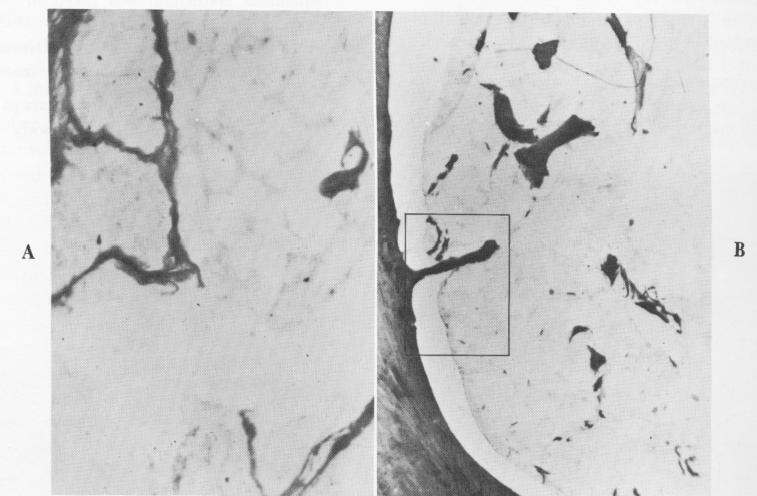

Fig. 4-81. A, High-power magnification of the interconnected strands extending from the fibrous membrane into the implant. B, A remarkably clear demonstration of a fibrous extension into the implant. C, Under even higher power, the nature of the extension is demonstrated. (Courtesy M. Hodosh.)

1 Fibrous strand extension into endosseous blade implant in mandible

2 Histology shows fibrous extension into lower endosseous blade implant